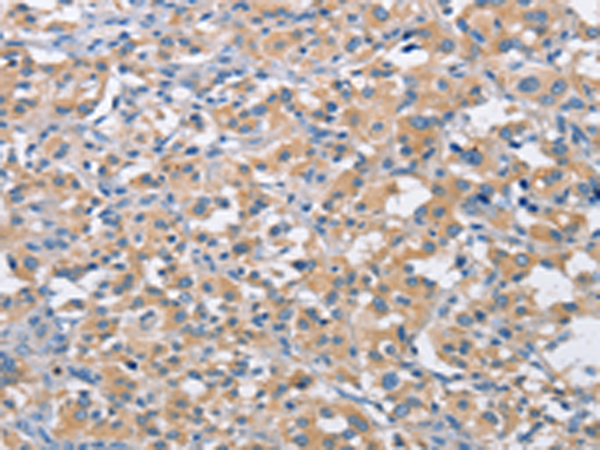

分类: 科研抗体货号: P07973别名: PIM应用: IHC反应种属: Human, Mouse, Rat